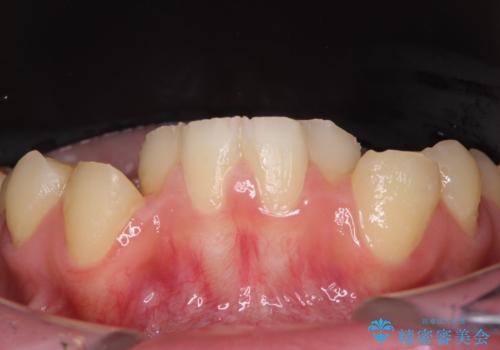

- 一時期の拒食症に伴い歯が酸で溶けてボロボロになってしまったとのことで来院された患者様です。

酸によりエナメル質の大半が溶けており、下顎前歯以外は酷いむし歯のような状態でした。

当初はほとんどの歯をむし歯治療のようにオールセラミッククラウンにて補綴治療を行う予定でしたが、仮歯に置き換えた時点で、口元の突出感や下顎前歯の叢生が気になるとのことで、上下左右の第一小臼歯4本を抜歯したワイヤー装置での抜歯矯正を行うこととしました。